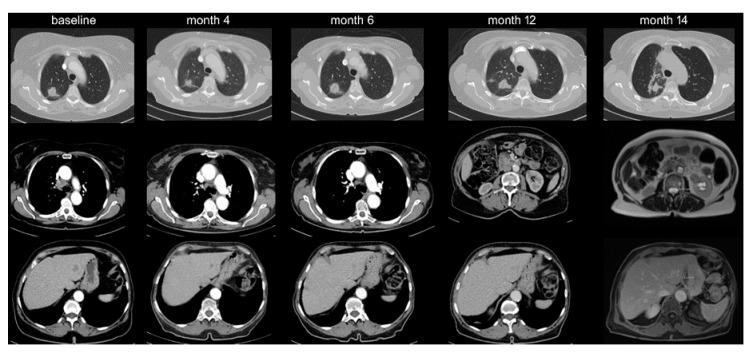

Oligoprogression (OPD) of non-small-cell lung cancer (NSCLC) occurs in approximately half of patients under targeted compounds (TKI) and facilitates use of regional therapies that can prolong survival. In order to characterize OPD in immunotherapy (IO)-treated NSCLC, we analyzed the failure pattern under PD-1/PD-L1 inhibitors ( = 297) or chemoimmunotherapy ( = 75). Under IO monotherapy, OPD was more frequent (20% vs. 10%, < 0.05), occurred later (median 11 vs. 5 months, < 0.01), affected fewer sites (mean 1.1 vs. 1.5, < 0.05), and involved fewer lesions (1.4 vs. 2.3, < 0.05) in the first compared to later lines. Lymph nodes (42%, mainly mediastinal) and the brain (39%) were mostly affected, followed by the lung (24%) and other organs. Compared to multifocal progression, OPD occurred later (11 vs. 4 months, < 0.001) and was associated with longer survival (26 vs. 13 months, < 0.001) and higher tumor PD-L1 expression ( < 0.001). Chemoimmunotherapy showed a similar incidence of OPD as IO monotherapy (13% vs. 11% at 2 years). Local treatments were applied regularly for brain but only in 50% for extracranial lesions. Thus, NSCLC oligoprogression is less common under IO than under TKI, but also favorable. Since its frequency drops later in the disease, regular restaging and multidisciplinary evaluation are essential in order to exploit the full therapeutic potential.

非小细胞肺癌(NSCLC)的寡进展(OPD)约发生在半数接受靶向化合物(TKI)治疗的患者中,这促进了可延长生存期的局部治疗方法的应用。为了明确免疫治疗(IO)的NSCLC中的OPD特征,我们分析了接受PD-1/PD-L1抑制剂(n = 297)或化疗免疫治疗(n = 75)患者的疾病进展模式。在IO单药治疗中,OPD更为常见(20% 对10%,P < 0.05),出现时间更晚(中位时间11个月对5个月,P < 0.01),与后续治疗线相比,在一线治疗中受影响的部位更少(平均1.1个对1.5个,P < 0.05),累及的病灶更少(1.4个对2.3个,P < 0.05)。淋巴结(42%,主要为纵隔淋巴结)和脑(39%)最常受累,其次是肺(24%)和其他器官。与多灶性进展相比,OPD出现时间更晚(11个月对4个月,P < 0.001),且与更长的生存期(26个月对13个月,P < 0.001)和更高的肿瘤PD-L1表达相关(P < 0.001)。化疗免疫治疗的OPD发生率与IO单药治疗相似(2年时为13%对11%)。局部治疗常用于脑转移,但仅50%用于颅外病灶。因此,NSCLC的寡进展在IO治疗下比TKI治疗下更少见,但预后也更好。由于其发生率在疾病后期下降,定期重新分期和多学科评估对于充分发挥治疗潜力至关重要。